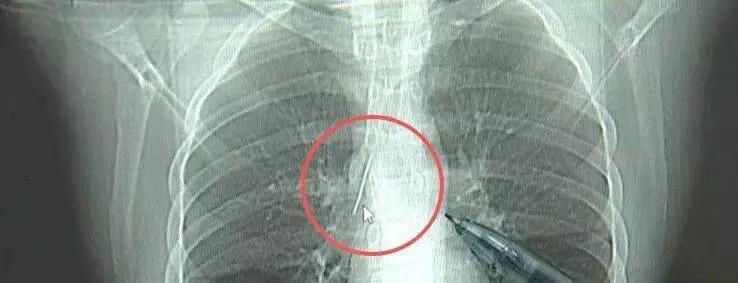

17岁小伙参军体检,竟在胸部发现一根5cm的缝衣针,位置极其凶险,这事儿简直太离